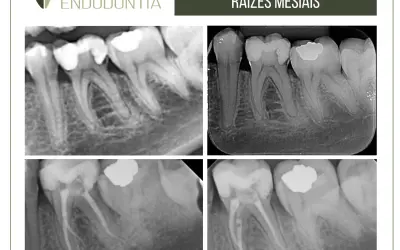

1.Radiografia inicial.

2.Análise e identificação dos seguintes elementos: pino, cimento, dente e resina.

3.Desgaste do núcleo e acesso ao retentor.

4.Início do desgaste do pino com uma ponta diamantada esférica de haste longa e de tamanho compatível, considerando a inclinação do dente e do pino.

5.Continuação do desgaste do pino com insertos ultrassônicos esféricos diamantados ou lisos (E9, E5, E4D e E2D – Helse Ultrasonic) com potência de 20 a 40%. Especial atenção deve ser dada à diferença de cor entre a dentina e o pino para evitar desgastes nas paredes radiculares.

6.O diâmetro das pontas de ultrassom deve ser compatível com o do canal em cada terço radicular. A realização de radiografias transoperatórias é fortemente recomendada.

7.Finalizado o desgaste do retentor, procede-se à limpeza do cimento remanescente nas paredes radiculares com um inserto ultrassônico liso na potência mínima.

8.Radiografia final.